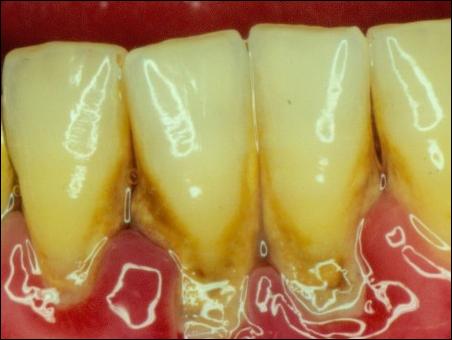

第二,是刷牙不好,尤其是下面的門牙,導致牙結石的滋生。

牙周病,即是牙齒周圍組織疾病。它是由一個炎癥點慢慢向周邊滲透發(fā)癥,最終導致整個的牙周都發(fā)炎的疾病。這是一個漸進的過程,發(fā)展極為緩慢,有可能在10年以,就像溫水煮青蛙一樣,等你發(fā)覺時,已經(jīng)來不及了,因此,拔牙是你不得不做出的最后選擇。

牙菌斑的細菌,會不斷地腐蝕牙槽骨,導致牙槽骨慢慢地被吸收,這個過程是不可逆的,你問一下牙醫(yī),所有的醫(yī)生都會這樣告訴你。軟組織缺了一塊,有可能再長出來,但你聽說過骨頭少一塊會再長出來的嗎?